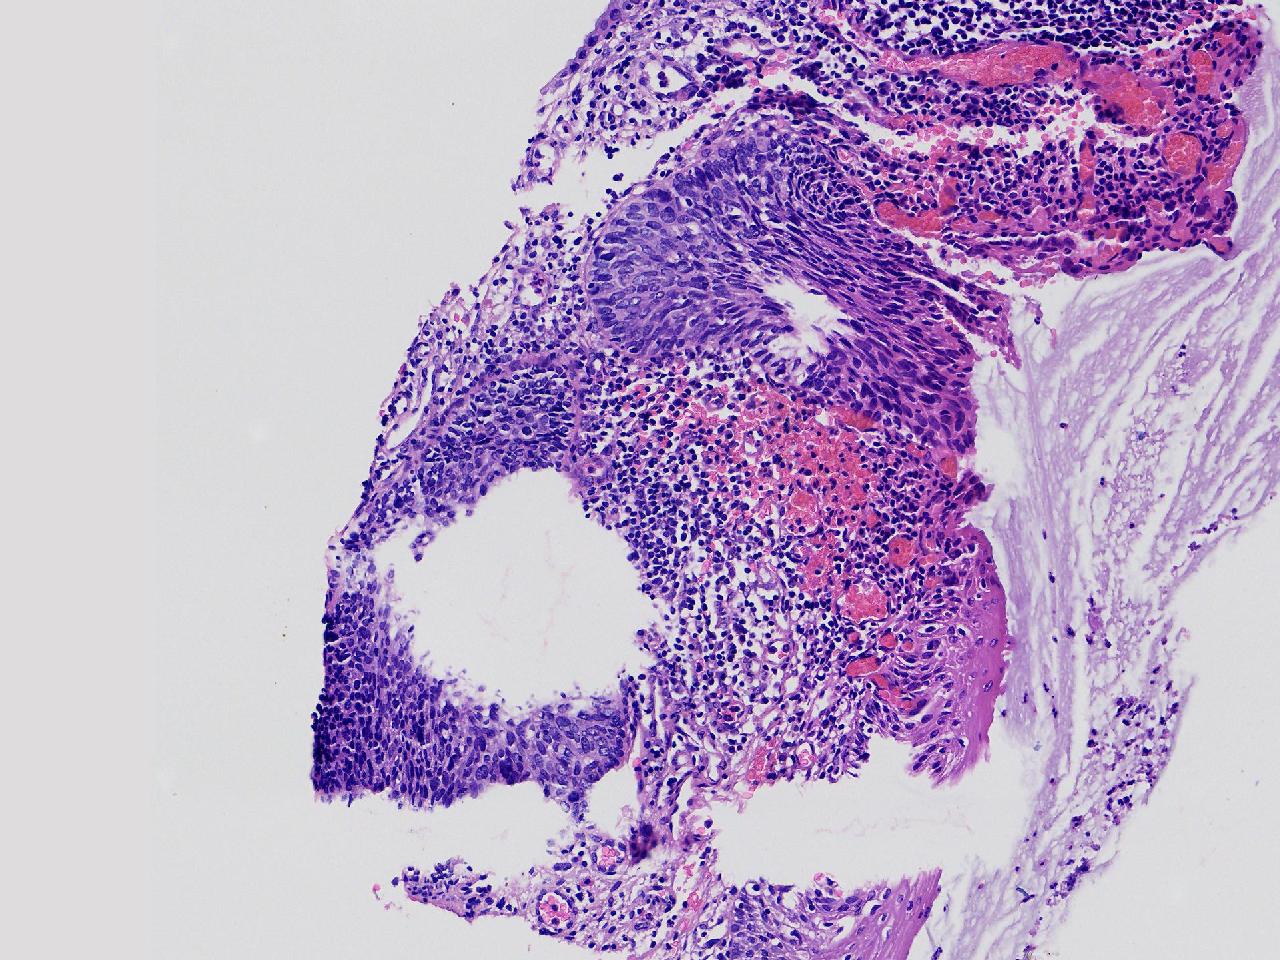

CIN1级? CIN2级?

女,49岁,宫颈11点活检,HPV:16+ 42+

宫颈11点活检。

灰白色不整形软组织1块。

图4

2级

2级,累腺。